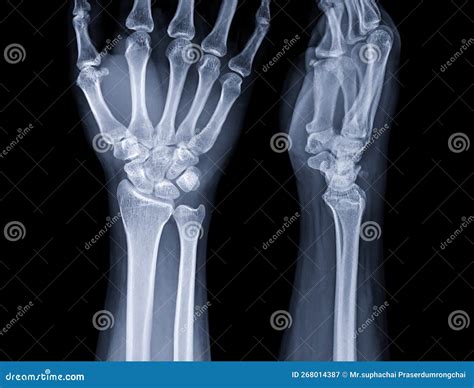

An MRI wrist joint scan is a non-invasive imaging technique that uses magnetic fields and radio waves to produce detailed images of the wrist. Unlike X-rays, which primarily show bones, MRI scans can visualize soft tissues such as ligaments, tendons, and cartilage. This makes MRI particularly useful for diagnosing conditions that affect these structures, such as fractures, ligament tears, and arthritis.

In some cases, alternative imaging techniques may be used instead of or in addition to MRI wrist joint scans:

• X-Rays: Useful for detecting bone fractures and certain types of arthritis.

• CT Scans: Provide detailed images of bones and can be useful for detecting fractures and bone abnormalities.

Each of these techniques has its own advantages and limitations, and the choice of imaging method will depend on the specific condition being investigated.